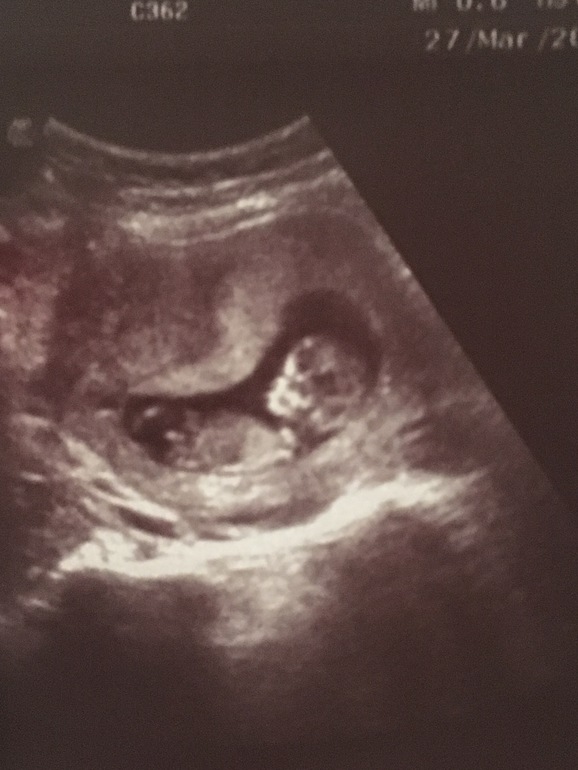

Я тут как понимаю ножки, а между ножек нечего не торчит. Предполагаю, что девочка. Но, это только так, в слепую. У, меня вот допустим в 14 недель узистка между ног увидела, что торчит что то, и я тоже видела. Но, она сомневалась, что это мальчик, уж какой то не мужской писюн торчал, предполагала, что клитор. И, это мне неуверенно говорила лучшая узистка

Мне тоже кажется, что девочка... У моего позначительнее там дело торчит.... И то я уже сомневаться начала. У нас скрининг 24го...жду)))))

Похоже на девочку. У нас два мальчика, там в 15-16 недель конкретное хозяйство между ног уже было)))

Первая мысль мальчик. Хоть ножки маленькие, но что то торчит, может пуповина. 🧐

Вижу торчит что-то 🙈 но фото не близкое,плохо видно. Да и срок маленький. Рано еще для точного ответа.

12 недель!!